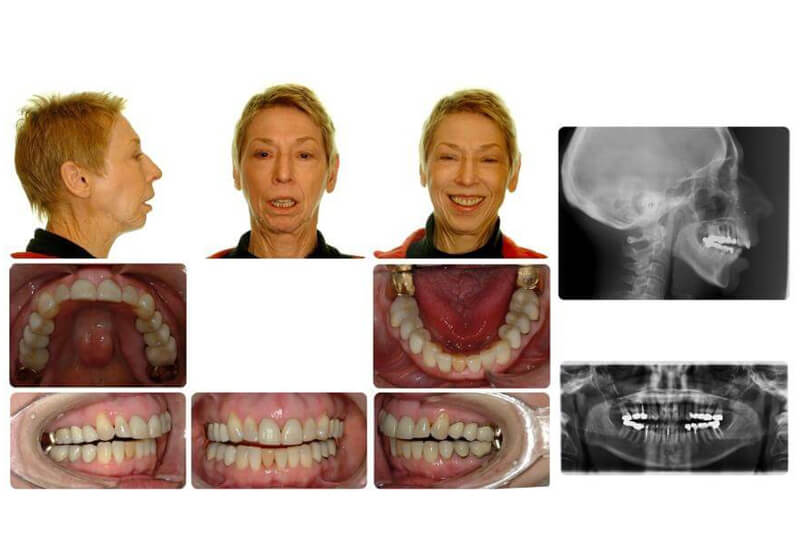

Case Report: